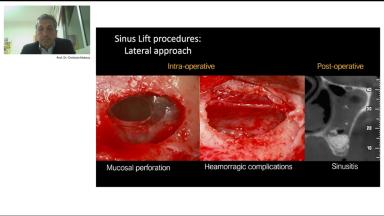

This lecture is brought to you by our industry partner mectron. It discusses lateral and crestal maxillary sinus floor elevation with a special emphasis on radiographic pre-operative planning to detect potential risk factors. It also highlights the importance of piezosurgical technology to augment surgical efficiency and to reduce perioperative complications.

- understand the importance of radiographic pre-operative planning to detect potential risk factors

- understand the step-by-step clinical procedures of both crestal and lateral sinus grafting techniques and the advantages of piezosurgery to minimize complications